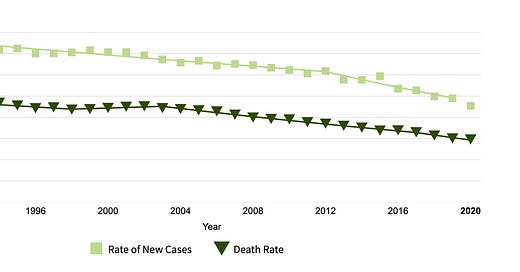

A woman’s lifetime chance of dying from ovarian cancer is about 1 in 130. The 5 year survival for ovarian cancer is 50.8%: